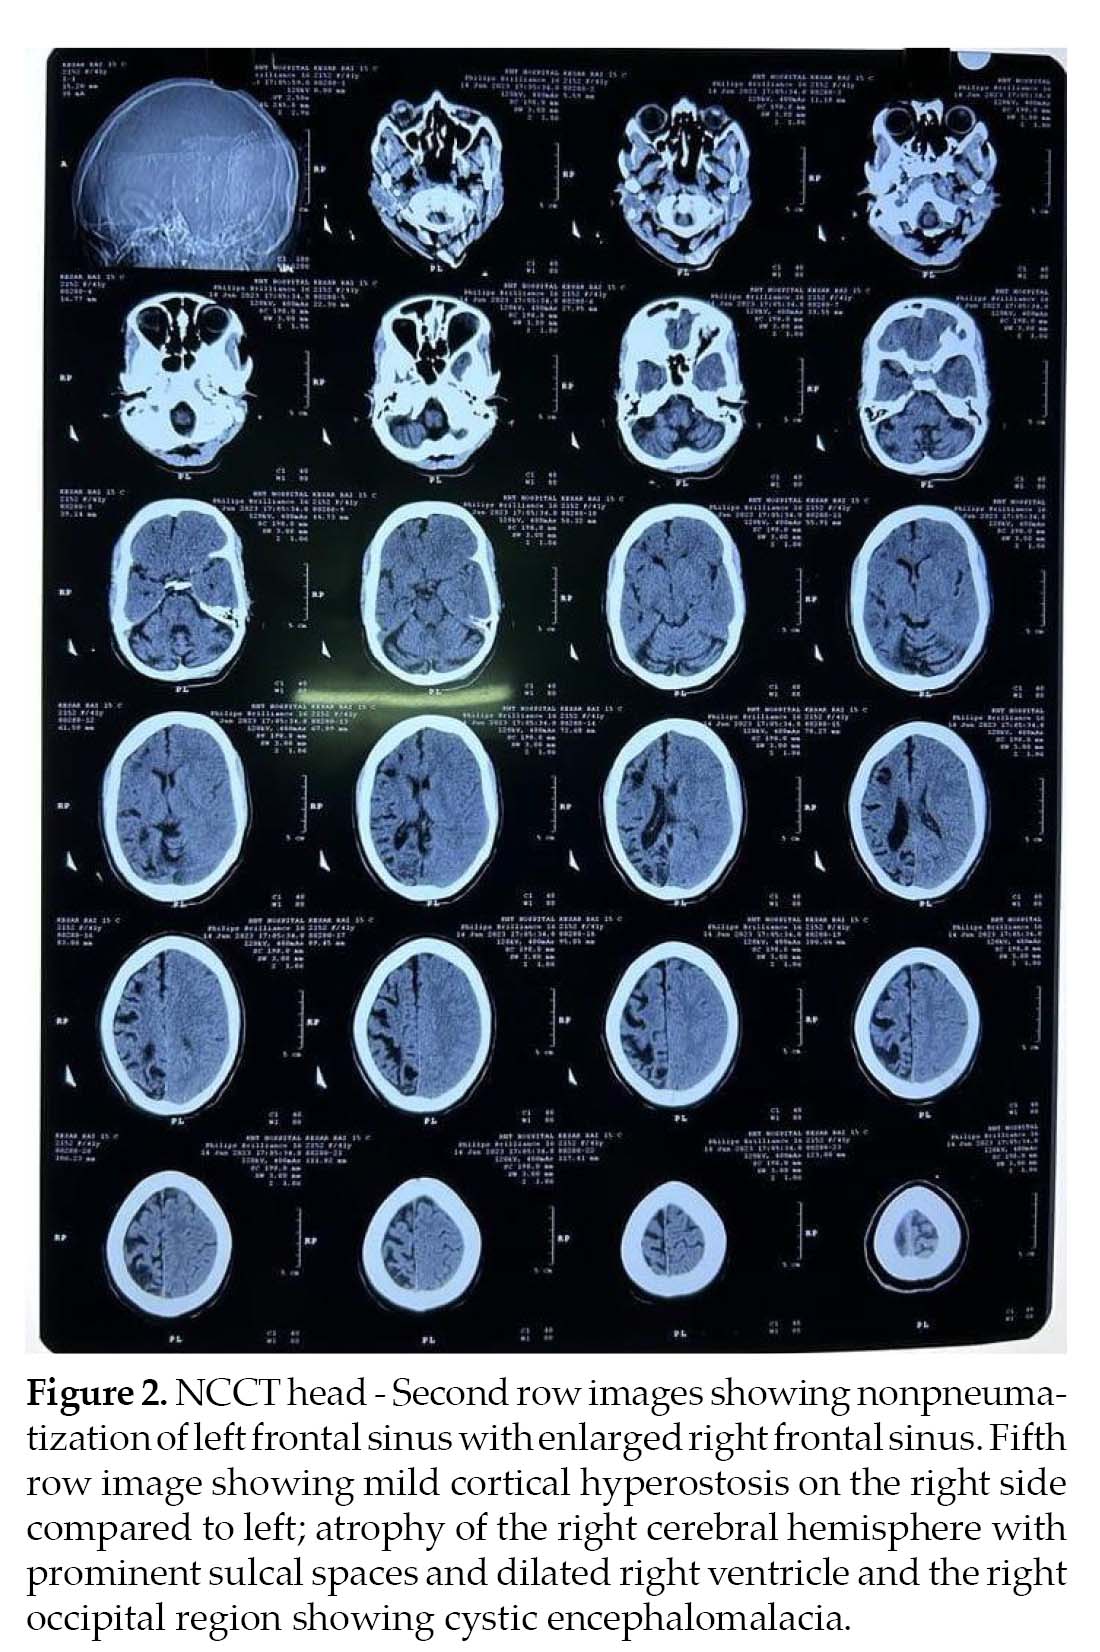

Noncontrast computed tomography (NCCT) (Fig. 2) head and MRI (Fig. 3) brain was performed, which revealed atrophy and prominent sulci and gyri of right cerebrum and cerebellum, with dilation of right lateral ventricle. There was mild cortical hyperostosis on the right side compared to the left. Nonpneumatization of left frontal sinus with enlarged right frontal sinus was seen. The left occipital region showed cystic encephalomalacia. EEG revealed epileptiform discharges in the form of paroxysmal generalized spike and wave having amplitude of 100-200 µV. Histopathology could not be done as the attendants were not willing. The patient was treated with tablet phenytoin 300 mg HS and tablet valproate 500 mg BD.